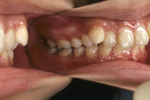

矯正の症例

1) 矯正前の状態

叢生(そうせい…歯がデコボコしたり、重なりあって生えていたりする状態)

開咬(かいこう…奥歯はしっかり噛んでいるが、上下の前歯が噛まずに隙間がある状態)